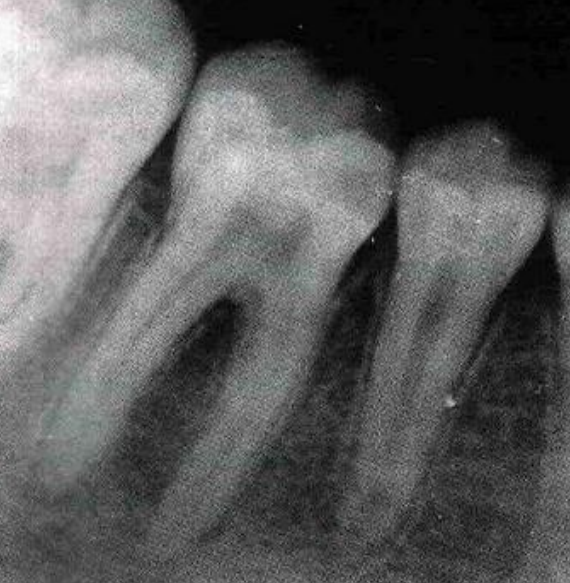

Présentation du patient : Jeune homme, 22 ans, en fin de traitement orthodontique fixe. Contrôle radiographique de dépose révèle une lacune d’aspect cupuliforme en cervical de la canine maxillaire gauche, sans symptomatologie douloureuse.

Problématique identifiée : Résorption cémentaire externe d’origine inflammatoire, probablement déclenchée par les forces orthodontiques excessives ou prolongées ayant lésé les fibres desmodontales et les cémentoblastes en surface. L’absence de cément à cet endroit a exposé la dentine à une colonisation clastique.

Prise en charge : Mise en place d’une contention passive immédiate pour éliminer tout stimulus mécanique. Contrôle tous les 3 mois par radio rétro-alvéolaire. Si progression : dépose chirurgicale de l’îlot de résorption, curetage, et obturation au MTA ou à l’hydroxyde de calcium selon profondeur. Si communication pulpaire : traitement endodontique.

Évolution attendue : En l’absence de progression, le CCFI peut combler partiellement la lacune sous contrôle radiologique. Une résorption progressive imposera une prise en charge chirurgicale.

Point clé illustré : Le cément cellulaire joue un rôle de réparation actif, mais cette capacité est limitée et dépend de l’absence de stimulus pathologique persistant.